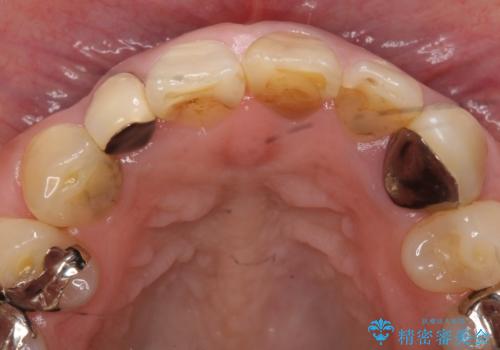

オールセラミッククラウン 下がってしまった前歯の歯茎の改善

- 他院で治療したところ、右上2番目の歯の歯茎が下がってしまったので診て欲しいといらっしゃった方の症例です。

診査の結果右上2は歯根が破折しており、それが原因で骨及び歯肉の吸収が起きていました。

このまま右上2の抜歯を行うとさらに歯茎が下がる恐れがあったため、歯の挺出によって骨レベルを回復した上で抜歯し、歯槽堤保存術(抜歯窩に人工骨を填入する手術)を行いました。

その後ブリッジによる補綴を行うことで、自然な見た目を再現することができました。